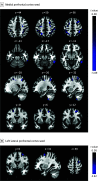

Results: Among the 345 children included in the analysis (177 boys [51.3%]; mean [SD] age, 6.58 [0.54] years), acetaminophen was detected in 199 meconium samples (57.7%), and ADHD was diagnosed in 33 children (9.6%). Compared with no acetaminophen, detection of acetaminophen in meconium was associated with increased odds of ADHD (odds ratio [OR], 2.43; 95% CI, 1.41-4.21). A dose-response association was detected; each doubling of exposure increased the odds of ADHD by 10% (OR, 1.10; 95% CI, 1.02-1.19). Children with acetaminophen detected in meconium showed increased negative connectivity between frontoparietal and default mode network nodes to clusters in the sensorimotor cortices, which mediated an indirect effect on increased child hyperactivity (14%; 95% CI, 1%-26%).